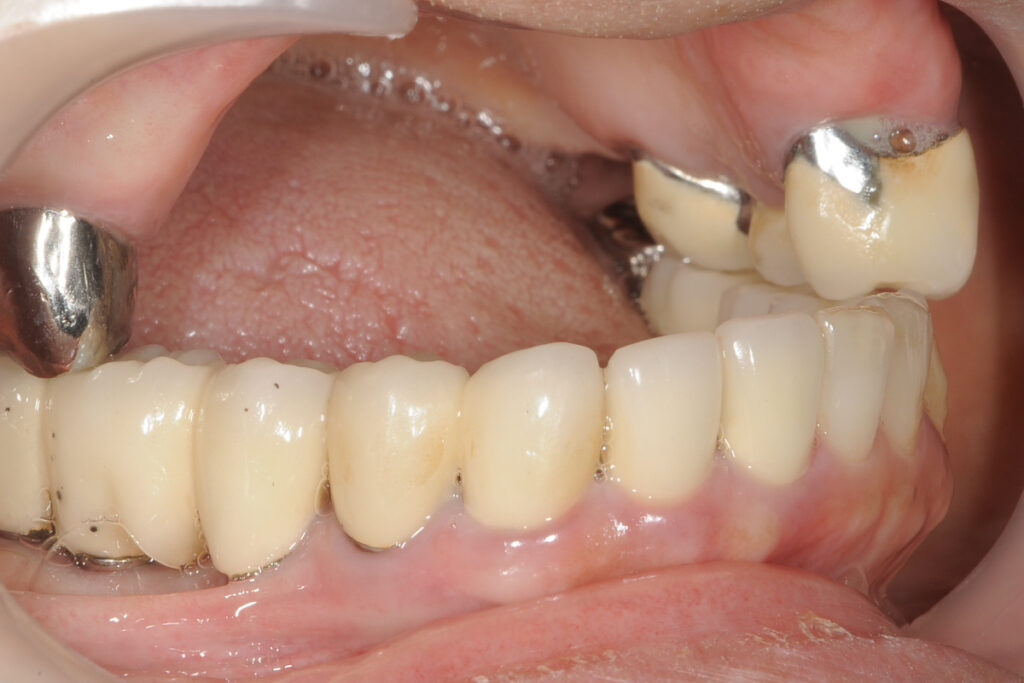

症例2|上顎骨が極端に薄いケース

――ザイゴマインプラントを「使わない判断」も含めて

■背景

60代男性。上顎ほぼ無歯顎。食事制限が続き、外食を避ける生活になっていました。他院では、「骨が極端に薄く、通常のインプラントは不可能」と説明されました。

■問題点の整理

- 上顎骨の骨量・骨質ともに厳しい

- 通常の骨造成では長期安定が見込めない

- 一方で、ザイゴマインプラントという選択肢は存在

- ただし、術式があることと、その人に適応できることは別

■当院での判断

吉留が検討したのは、「ザイゴマを使えるか」ではなく、「使った場合に、その人の生活条件で管理できるか」です。

■選択した治療

- 条件を満たすことを前提に、ザイゴマインプラントを用いた治療

- 通常法を無理に拡張する選択は行わず

■結果としての状態

噛む機能の回復とともに、長期管理を前提とした設計が成立しました。「設計が成立」とは、手術が終わったという意味ではありません。10年単位で維持できる見通しが構造として成立したということです。